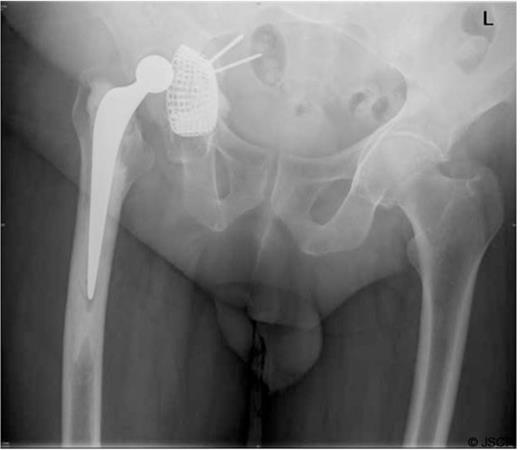

He was admitted to the High Dependency Unit for post operative recovery where he spent 6 days. On return to the elective ward, he made an uneventful recovery and required anticoagulation with warfarin for six months to protect the IVC filter. The most recent radiograph of his pelvis (Figure 4) showed excellent incorporation of the bone graft.